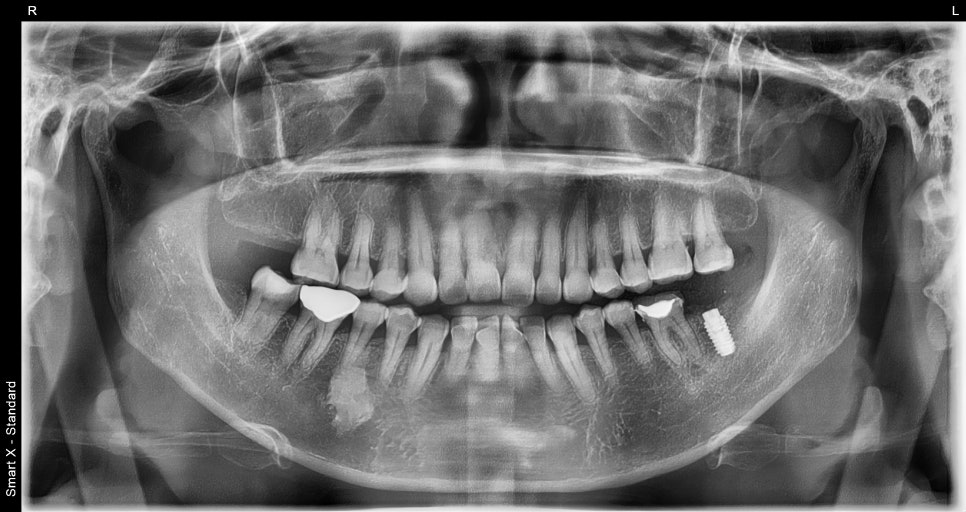

Recovery and second surgery process

After implant placement, time is needed for the bone and implant to

integrate.

After about 2 to 3 months, a second surgery is performed

to connect the implant above the gums.

Important prosthetic treatment for molar implants

The completion of implant treatment is determined at the prosthetic stage.

In this case,

custom abutment applied

zirconia prosthesis fabricated

occlusal adjustment

were performed.

Because molar implants must withstand chewing force,

accurate occlusion is very important.

Even the slightest occlusal differences are adjusted to ensure stability.

Treatment that also considers adjacent teeth

in addition to the implant, crown treatment on the adjacent tooth

was also performed.